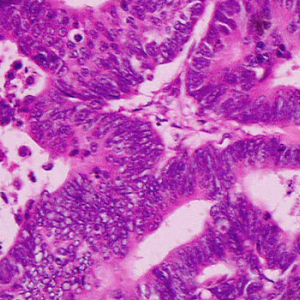

Cancer

The Cancer research program conducts highly collaborative basic and translational studies to uncover mechanisms of cancer development and create novel diagnostics and therapies across diverse tumor types cancer research.